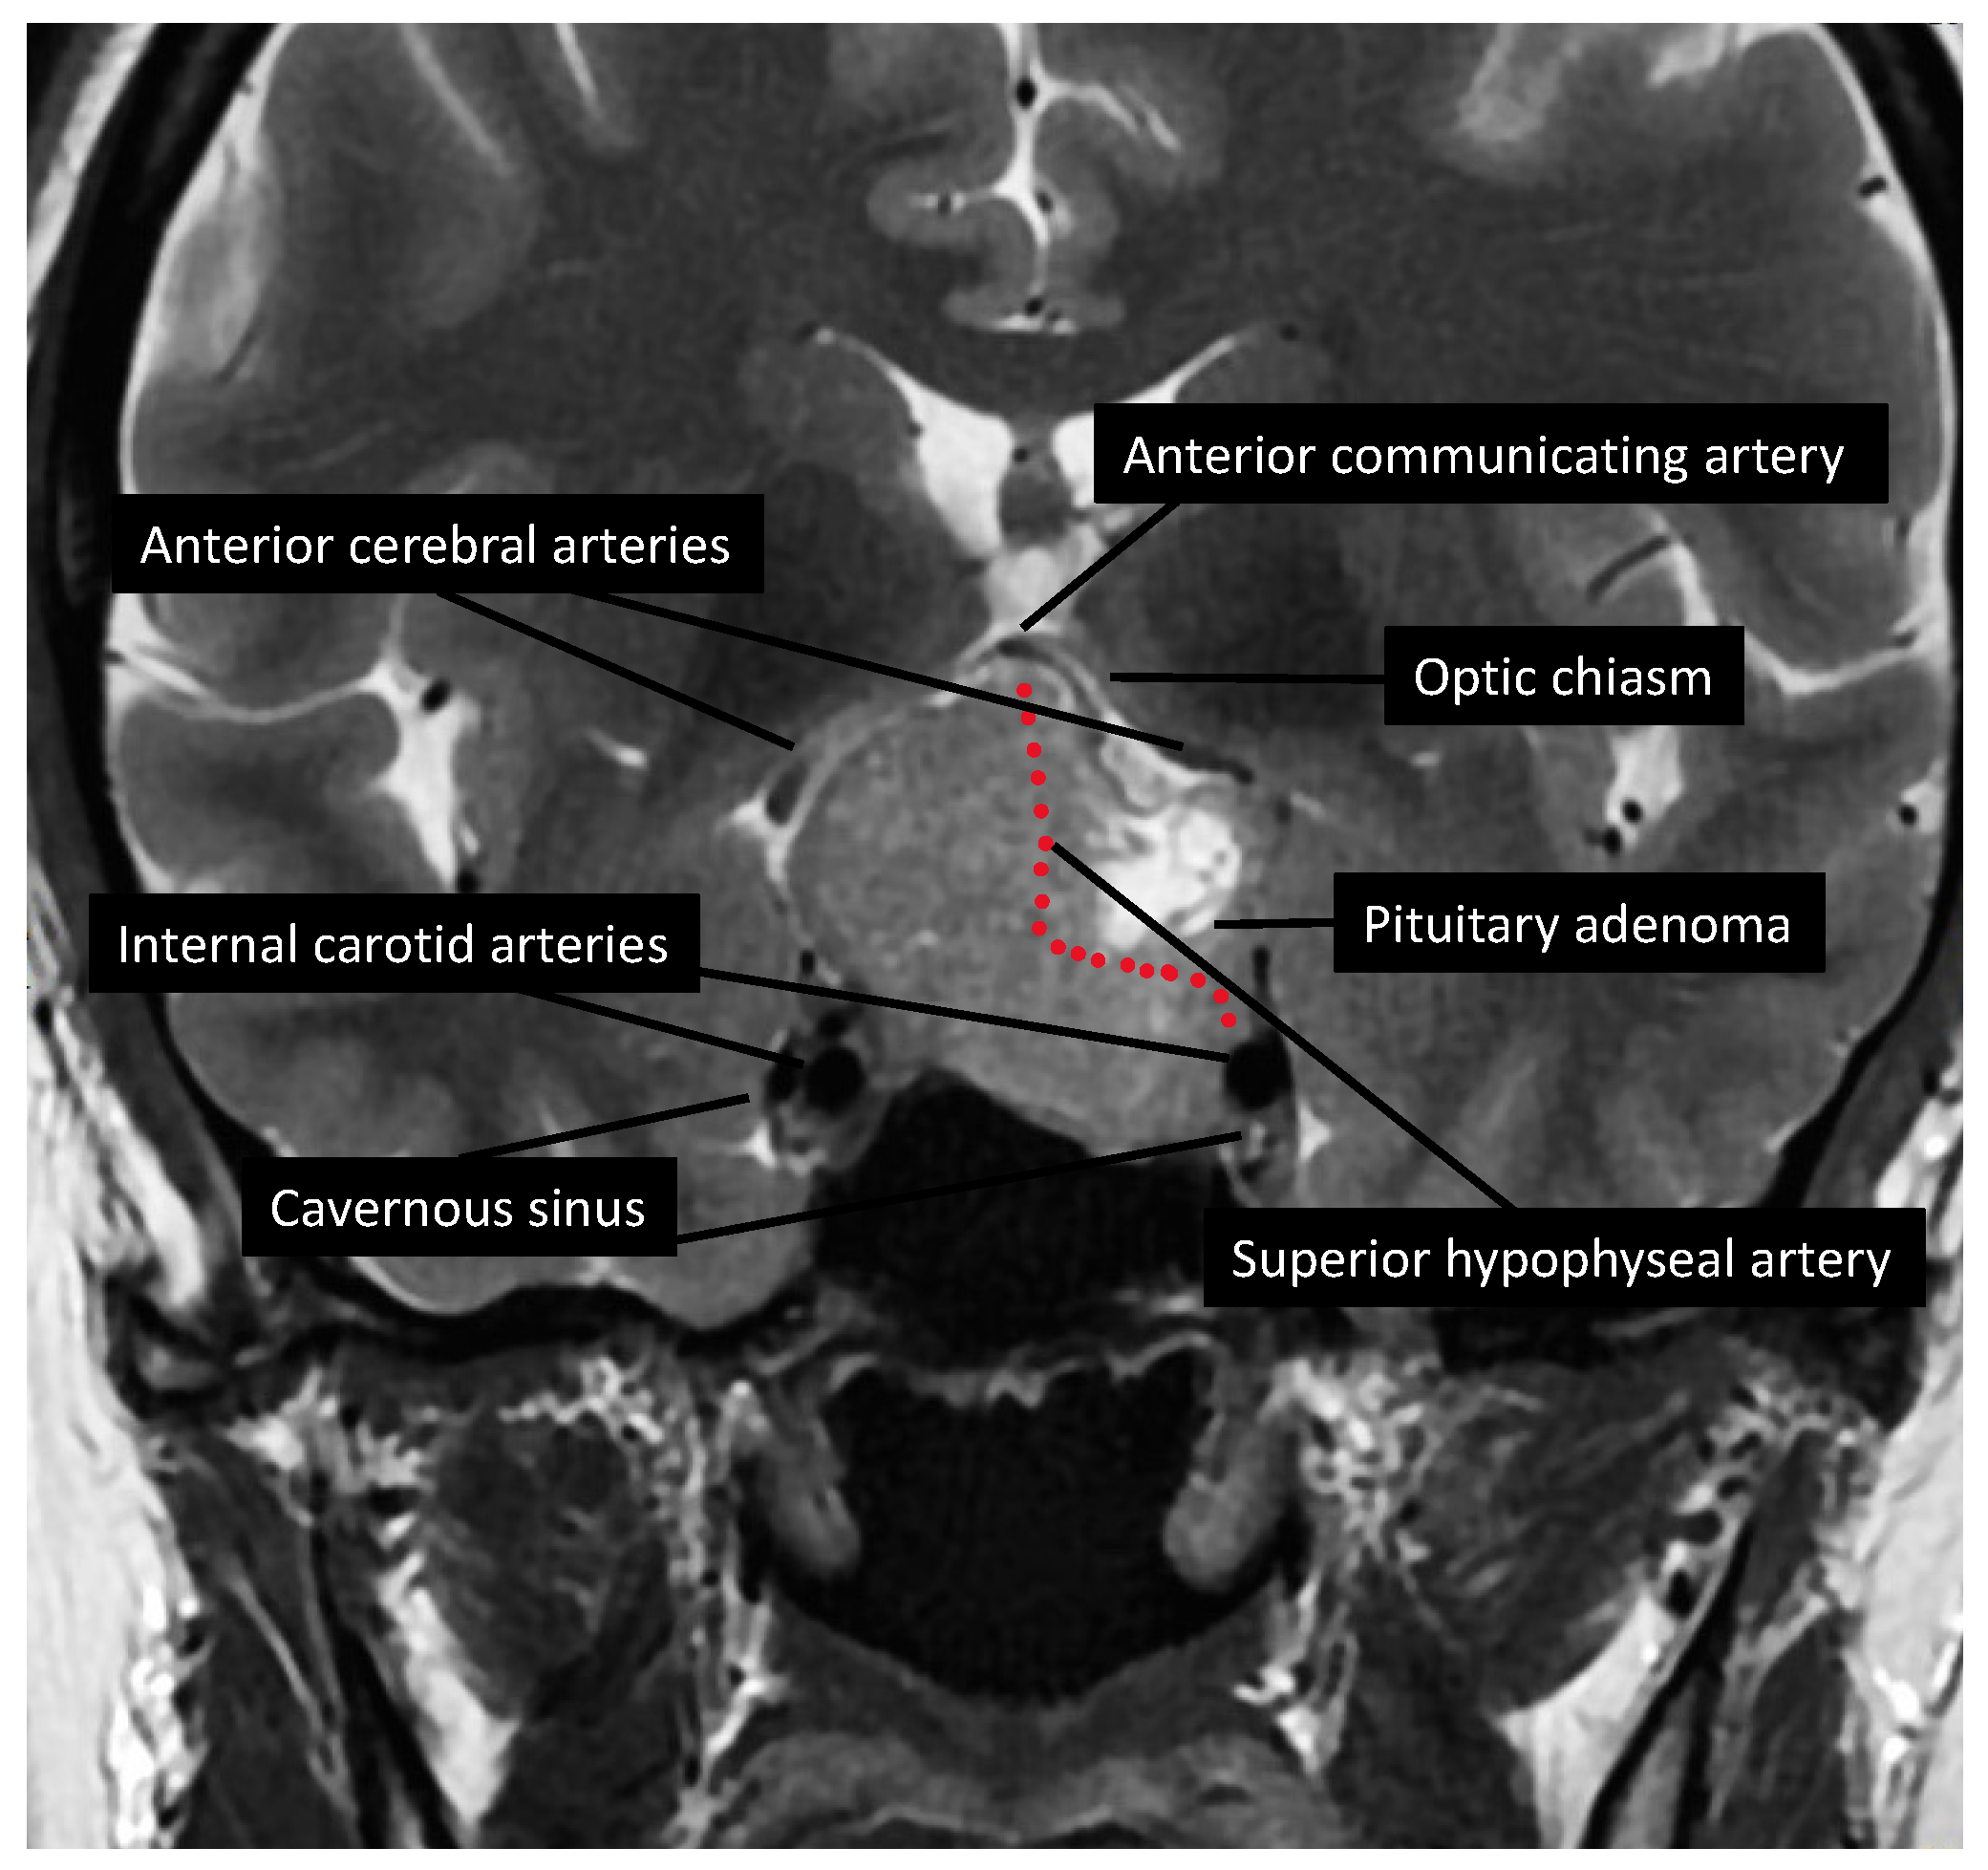

4.1. The Mechanical and Vascular Theories

4.2. Main Results